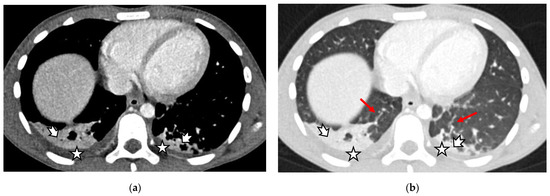

- Size abnormalities of the liver and spleen (Figure 3), kidneys, and pancreas.

- Parenchymal abnormalities of the solid organs (heterogeneous echotexture of the liver or spleen, increased echogenicity of the renal parenchyma compared to the liver, and abnormal or heterogeneous attenuation).